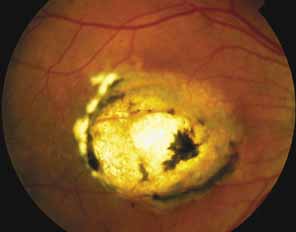

Other forms of central choroidal dystrophy exist that do not show the discrete oval lesions of typical central areolar choroidal sclerosis. These forms of central choroidal choriocapillaris atrophy often present with progressive pigment epithelial mottling and patchy choriocapillaris atrophy initially limited to the macula (Figs. 2A and 2B). With time, the atrophy enlarges and eventually encompasses the entire posterior pole (Fig. 2C). For this form of central choroidal atrophy, a gradual transition usually occurs from atrophic central pigment epithelium and choriocapillaris to essentially normal retina and choroid in the peripheral fundus.

Bietti's crystalline dystrophy (MIM No. 210370) of the cornea and retina is an autosomal recessive disorder that is characterized by the presence of crystals of unknown composition in the stroma of the peripheral cornea and at several layers of the retina (Figs. 3A and 3B).23 The disease can be subdivided into regional and diffuse forms, and the lack of any reports of the two patterns in the same family suggests genetic heterogeneity and not just variable expressivity.24,25 The regional form begins in midlife as pericentral scotomas that cause difficulty reading and reduced central visual acuity. Peripheral retinal function is retained and the electroretinogram and electrooculogram are normal or near normal even in moderately advanced disease. The fundus appearance and fluorescein angiogram reveal regional loss of pigment epithelium and choriocapillaris limited to the posterior pole (Figs. 3C and 3D). The finding of abnormal crystals in leukocytes indicates that this is a systemic metabolic disorder.24